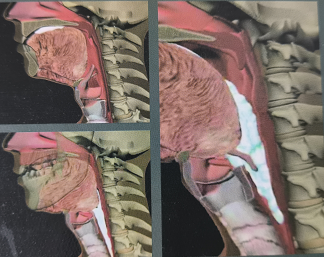

本圖來源于醫(yī)療用書《吞咽障礙評估與治療》,版權歸原作者所有

吞咽障礙是由于下頜、雙唇、舌、軟腭、咽喉、食管等器官結(jié)構(gòu)和(或)功能受損,不能安全有效地把食物送到胃內(nèi)取得足夠營養(yǎng)和水分的進食困難。